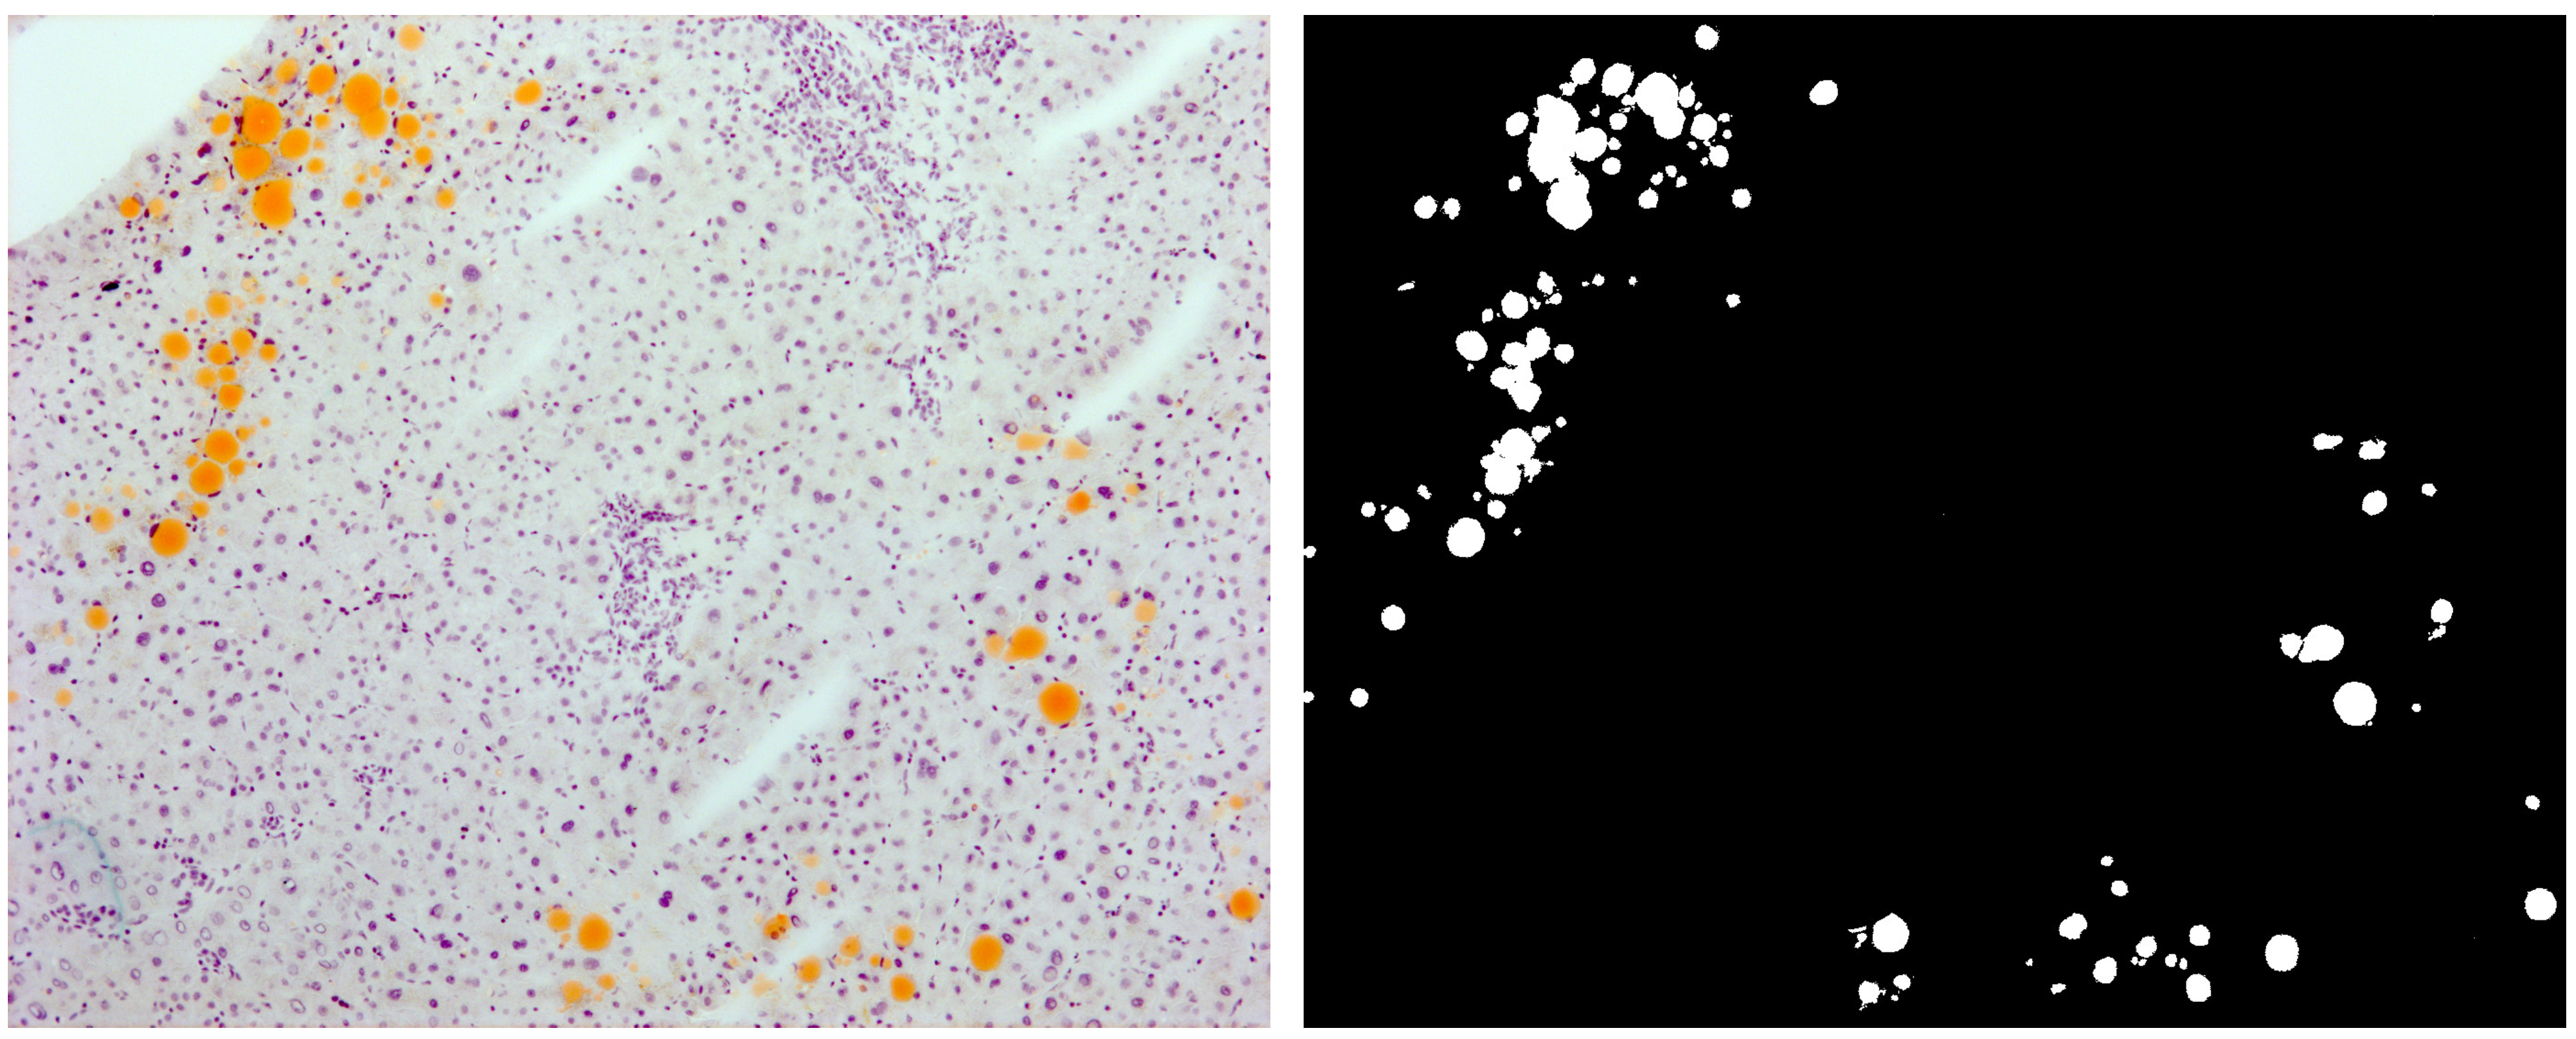

4.1. Liver Samples and Histochemical Procedures

4.2. Imaging

4.3. Generating Learning Models